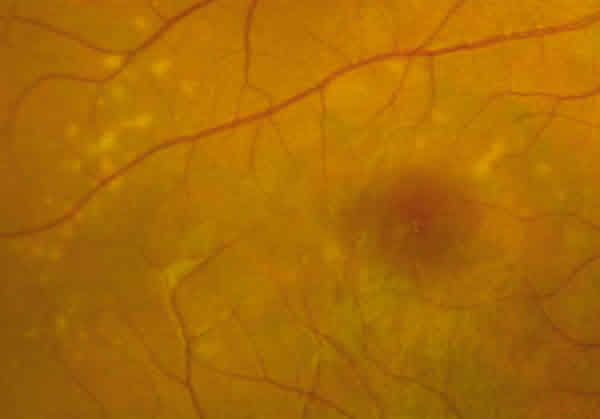

En la oftalmoscopía tenía un parénquima retiniano aparentemente normal con algunas zonas grisáceas subretinianas en el polo posterior de AO y en el OD unos flecos amarillentos perimaculares (figs. 2 y 3).

Fig. 2. Detalle de los flecos retinianos perimaculares en OD del caso 1.